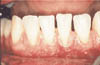

Fig 2a: Preoperative view of biopsy site.

Practitioners may have the occasion to perform a soft tissue biopsy and submit the sample for histologic examination and diagnosis (Fig. 2(a)). The use of sutures for wound closure may be very difficult or impractical in certain situations. Periodontal dressings may be difficult to apply and retain. Bleeding may also be difficult to control. In my practice, following the soft-tissue biopsy, I apply a thin layer of cyanoacrylate to the biopsy site. The material is effective as a surgical dressing during the early healing phase. (Fig. 2(b)). Appropriate post-operative care instructions are given and the patient is asked to return for follow-up (Fig. 2(c)).